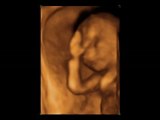

Selda ve Özer'in oğlu (4 Boyutlu Ultrason)